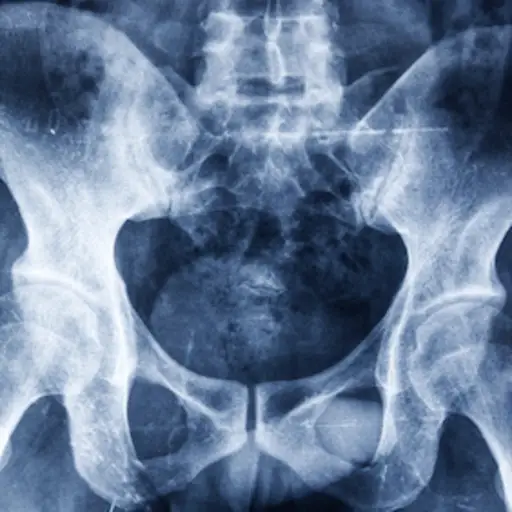

骨质疏松风险因素:年轻女性现在可以做什么来降低风险

骨质疏松症是一种这种疾病会使骨骼变薄变弱,增加骨折的风险。一个常见的误解是骨质疏松症是一种“老年人疾病”。但是,虽然大多数女性直到晚年才发现这种影响,但你生命早期的因素会直接导致你日后患上这种疾病的潜力。虽然一些导致骨质疏松的风险因素无法改变,但你可以采取一些措施来帮助自己减少你的风险.请继续阅读,了解他们。